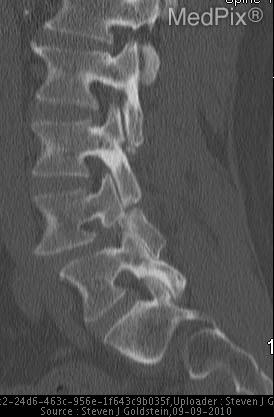

Spondylolisthesis

This occurs when one vertebrae slips forward in relation to the vertebrae below it and may be asymptomatic or cause increased pain across the low back and into the buttocks and legs (including hamstring spams). This displacement of the vertebrae can press on nerves causing the pain. Spondylolisthesis is common in adolescent athletes with back pain and also in people over 65 that have experienced degeneration of their discs. Physical therapy to strengthen your back muscles and improve your stability is very important and the most common treatment technique.